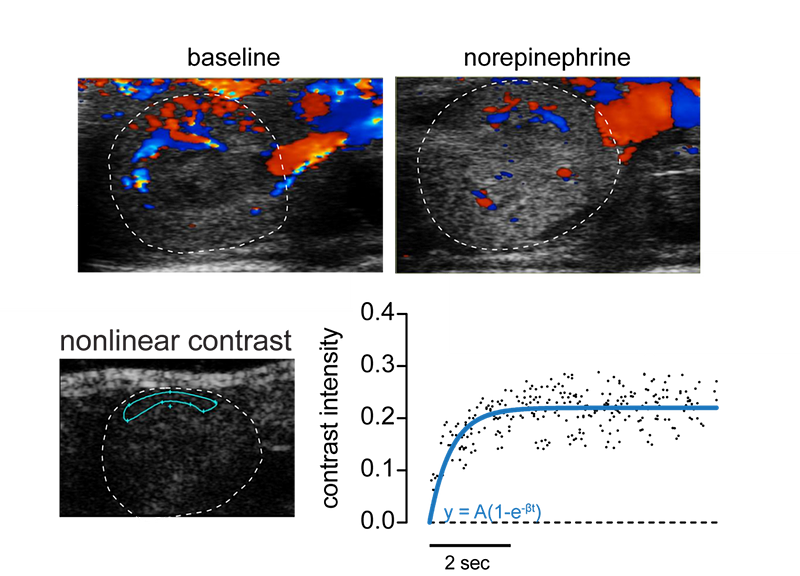

Measuring Renal Blood Flow and Tissue Perfusion

The Center's Non-Invasive Imaging Core houses a Vevo 3100 high resolution in vivo imaging system. This system is specialized to view extremely small physiological structures in mice in real-time. Coupled with infusion of a contrast agent, we can assess kidney size, blood flow, and tissue perfusion.